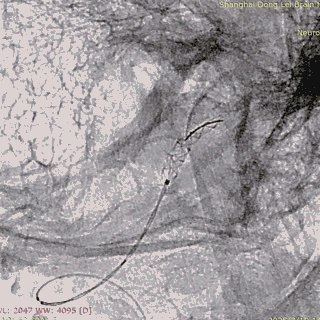

微导丝带017 Accessway微导管上高至远端。

第一枚2*20支架通过017支架微导管到位。

支架远端打开。

支架远端打开情况。

支架中段打开,过50%释放标记点。

造影显示支架整体打开良好。

支架完全释放。

微导管沿推送杆通过支架,撤出推送杆,保留通路。

造影显示支架打开良好,准备桥接第二枚支架。

第二枚3*25支架沿017支架微导管上高。